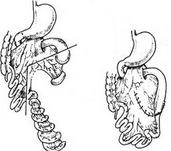

肺隔离症

628健康网为您分享有关肺隔离症的症状,肺隔离症的治疗方法,肺隔离症的预防知识,肺隔离症的症状图片,肺隔离症吃什么药,肺...